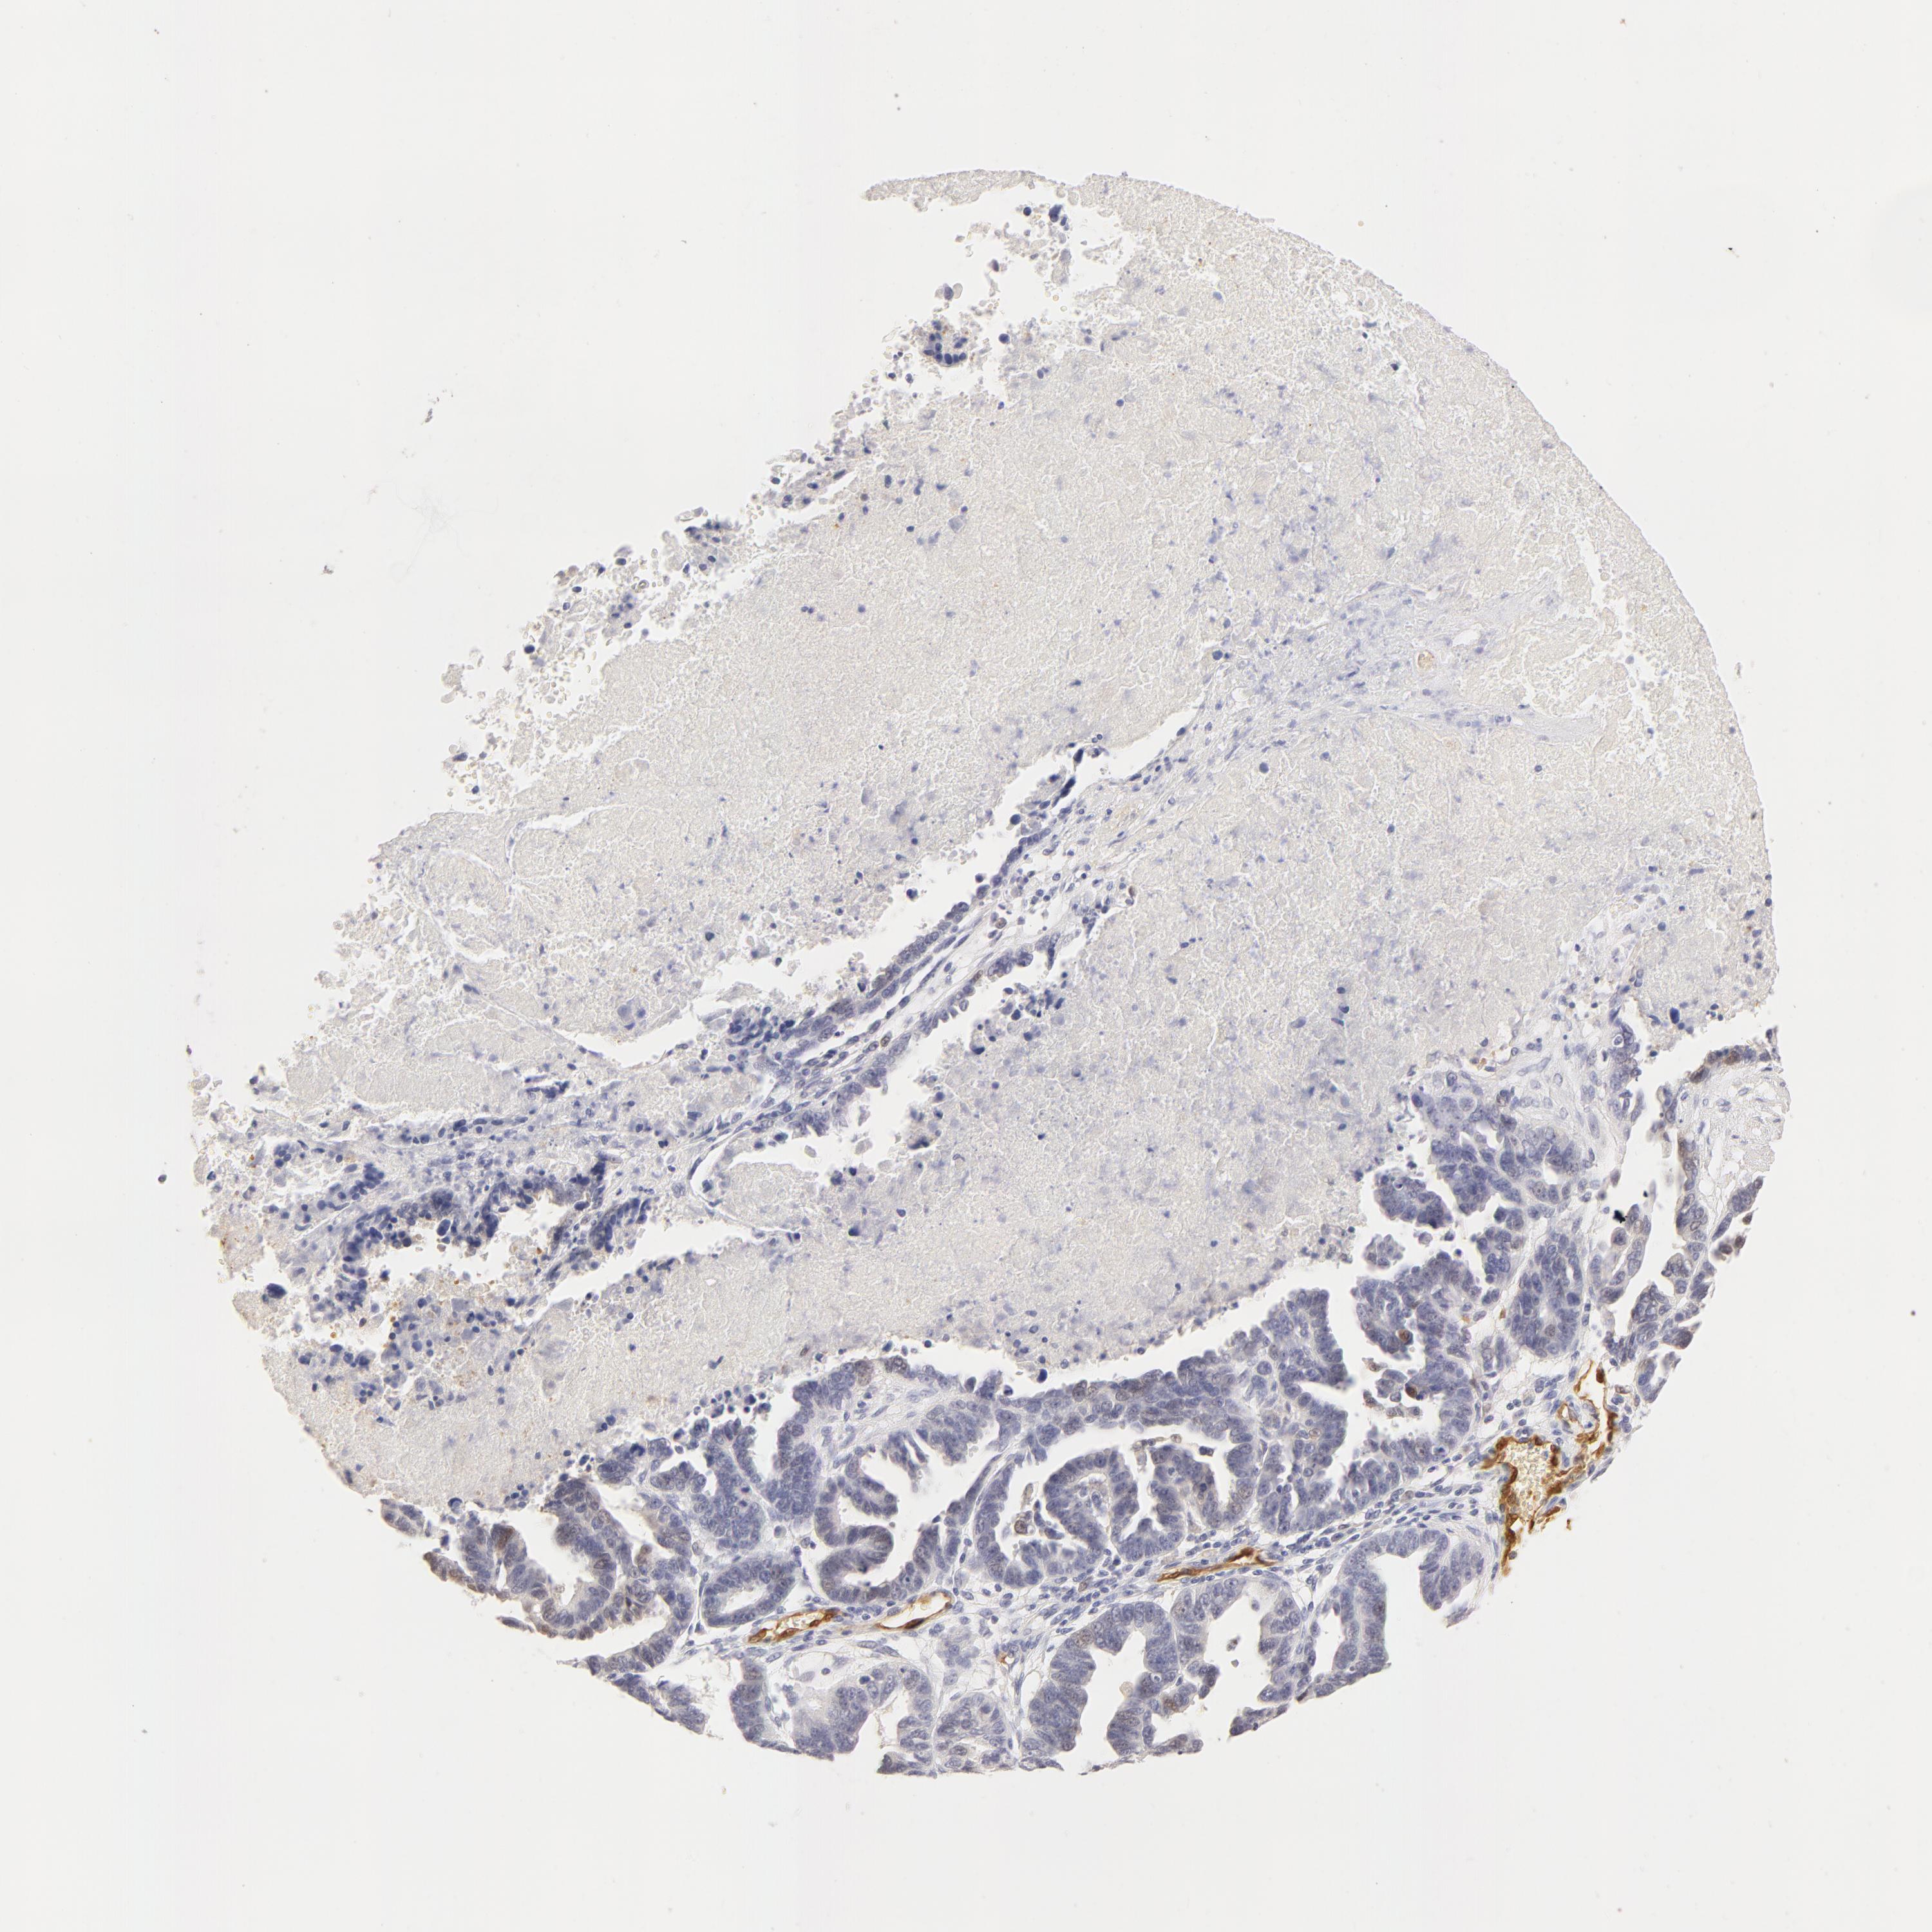

OVARIAN CANCER - Protein expressioni

A mouse-over function shows sample information and annotation data. Click on an image to view it in a full screen mode. Samples can be filtered based on level of antibody staining by selecting one or several of the following categories: high, medium, low and not detected. The assay and annotation is described here.

Note that samples used for immunohistochemistry by the Human Protein Atlas do not correspond to samples in the TCGA dataset.

Antibody stainingi

Antibody staining in the annotated cell types in the current human tissue is reported as not detected, low, medium, or high, based on conventional immunohistochemistry profiling in selected tissues. This score is based on the combination of the staining intensity and fraction of stained cells.

Each image is clickable and will lead to virtual microscopy that enables deeper exploration of all samples and also displays staining intensity scores, fraction scores and subcellular localization as well as patient and tissue information for each sample.

Antibody HPA001550

Antibody CAB010102

Staining

High

Medium

Low

Not detected

Intensity

Strong

Moderate

Weak

Negative

Quantity

>75%

75%-25%

<25%

None

Location

Nuclear

Cytoplasmic/membranous

Cytoplasmic/membranous,nuclear

Carcinoma, endometroid

Cystadenocarcinoma, serous, NOS

Cystadenocarcinoma, mucinous, NOS

Carcinoma, NOS